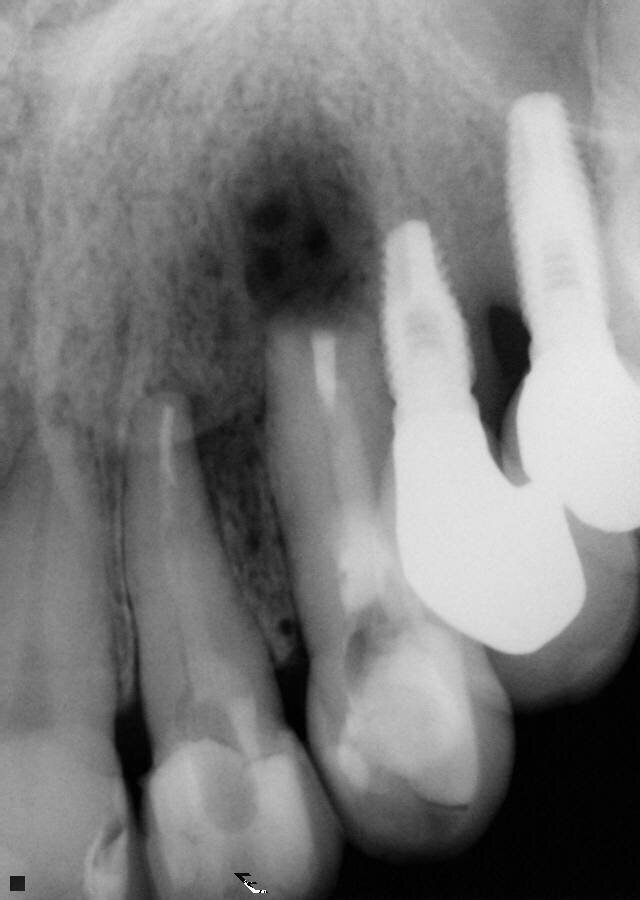

Fig. 4: Periapical radiograph during the root-end surgery verifying the complete root-end filling.

After the complete filling of the cavity is observed, the material excess is removed by washing the cavity with saline solution (Fig. 4).